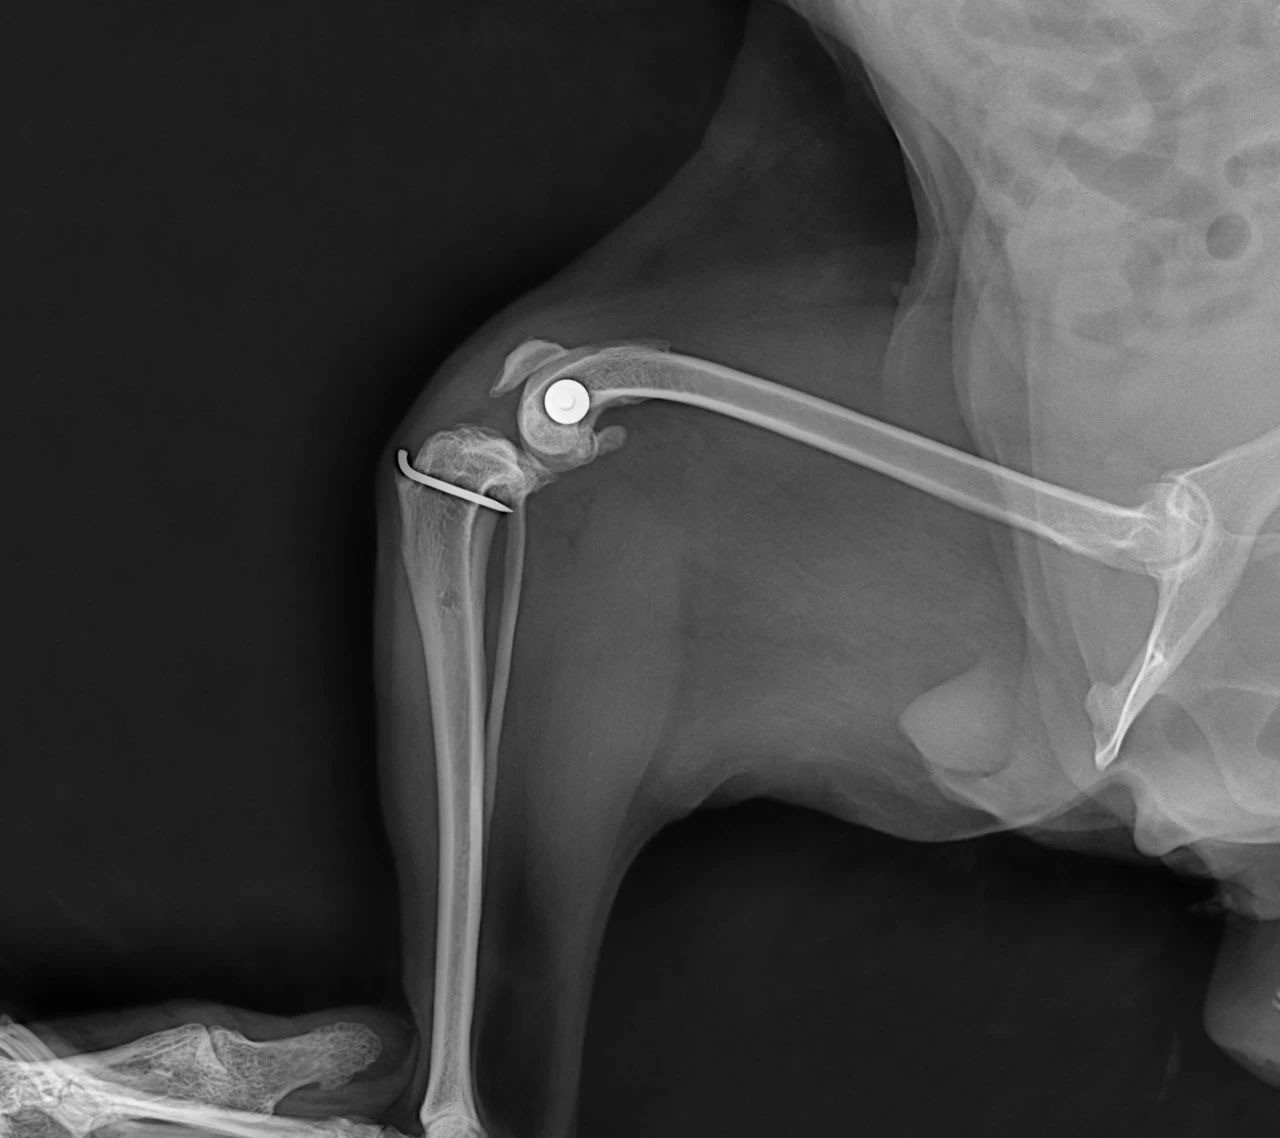

Figures 4 & 5. Post-op X-rays